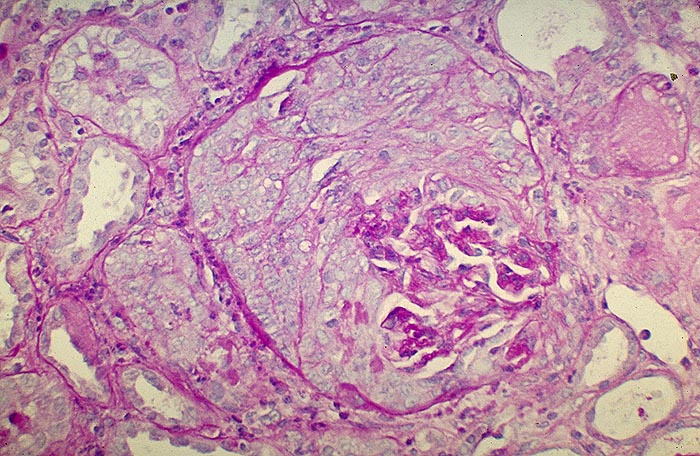

PathoPic – image database / PathoPic ID 1951 - Extrakapillär betonte Glomerulonephritis: globaler Halbmond

Extrakapillär betonte Glomerulonephritis: globaler Halbmond

Der Kapselraum des Glomerulus wird durch proliferierte Zellen eines globalen Halbmondes, der das gesamte Schlingenkonvolut umgibt, vollständig ausgefüllt. Die Glomerulusschlingen sind im Bereich des Gefässpols zusammengesintert. Keine Zellvermehrung im Schlingenkonvolut.

Beim Goodpasture Syndrom kommen nicht nur in den Nieren, sondern auch entlang der alveolären Basalmembran ultralineare Ablagerungen von Antibasalmembran Antikörpern vor. Gehäuft bei Rauchern, nach Virusinfekten, nach Rifampicin oder bei malignen Tumoren.